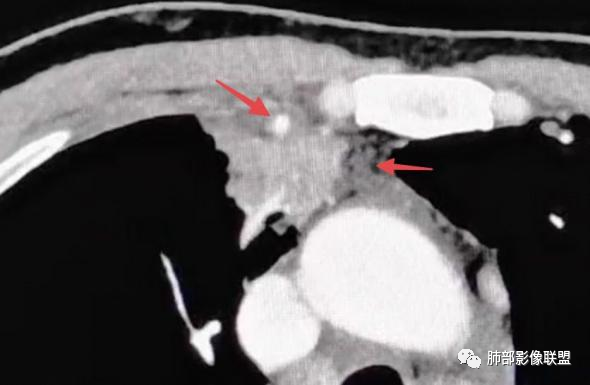

Coke with ice分析

1、补充一点点征象,欢迎拍砖。

病变诊断炎性是比较明确的。老师们说了很多依据,我再加几个征象

1

红箭-支气管分叉间条形高密度

2

这个脂肪间隙很模糊。

3

这里也是。还有血管增粗。

4

增大淋巴结

很多增大的淋巴结,强化方式一致均匀,

未见明确坏死,融合不明显,没有明确的分布优势。

5

这里是软组织密度,纵隔内突入

我觉得这里可以怀疑是栽桩。